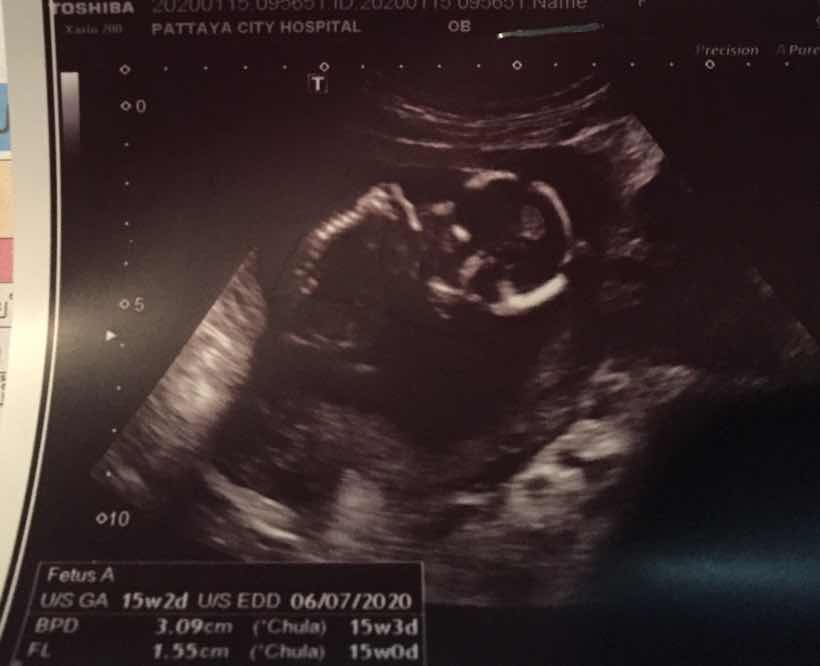

15W2dค่ะ

Post reply image